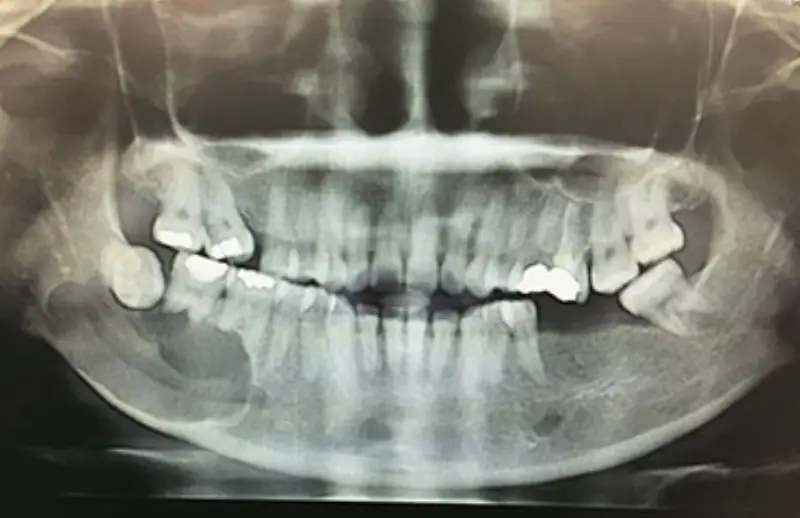

ذهبت إلى العيادة قبل بضعة أيام وأنا أشعر بالألم، ورحبوا بي عند المدخل وكان الأطباء مهتمين. بعد إجراء الأشعة السينية، تم عمل الخطط اللازمة لي. مكان يمكنك فيه الحصول على قيمة أموالك. غادرنا ونحن راضون أكثر باهتمام مديرة العيادة السيدة دويغو. شكراً لك أوزبودنت (: